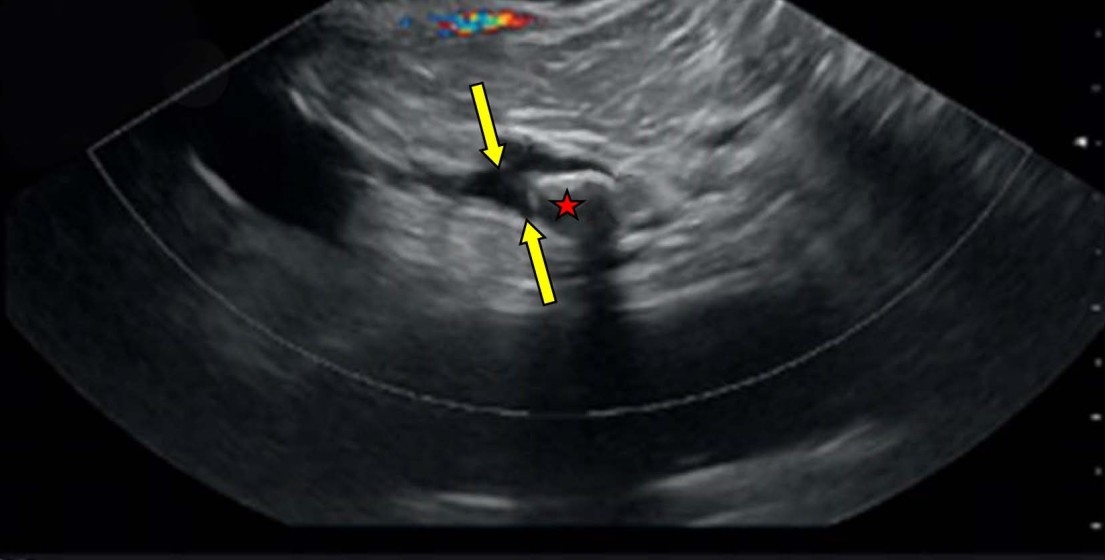

Пациент был дообследован в объеме эндосонографии, при которой было выявлено расширение главного панкреатического протока в головке — до 13 мм, в теле — до 10 мм, в хвосте — до 6 мм, а также наличие в его просвете крупного конкремента размером 18ђ12 мм неправильной продолговатой формы, локализованного в 1–1,5 см выше устья вирсунгова протока (рис. 7). Таким образом, диагноз хронического калькулезного панкреатита, крупного ВЛ и выраженной дилатации ГПП был подтвержден.

Рис. 7. Эндосонография поджелудочной железы конвексным эхоэндоскопом — в просвете расширенного вирсунгова протока (указан стрелками) крупный конкремент с яркой акустической тенью (отмечен звездочкой)